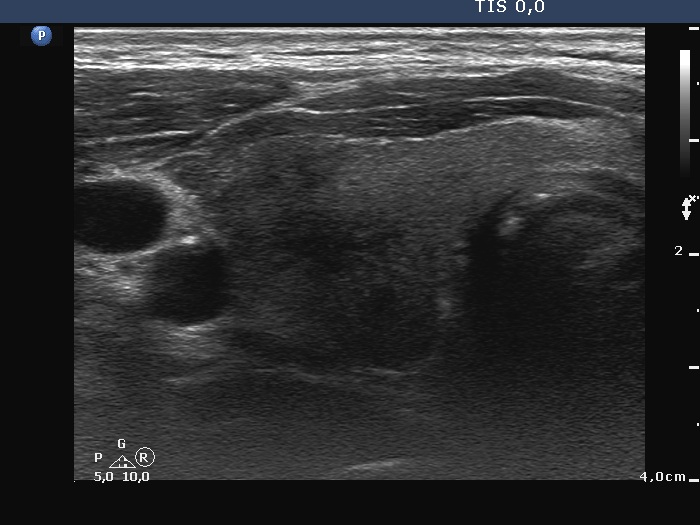

Initial examination (first row of images):

Clinical presentation: A 43-year-old man was referred for evaluation of neck complaints which have started 6 weeks ago when both sides of the neck became tender and occasionally painful. The patient noticed recurrent fever. Non-steroid anti-inflammatory drugs had only temporary effect.

Palpation: Both lobes were hard and painful on palpation.

Laboratory examination: TSH 0.02 mIU/L, FT4 28.7 pM/L, aTPO < 28 U/mL, CRP 55.7 mg/L

Ultrasonography: Both lobes had hypoechoic areas which showed ill-defined borders. The echogenicity index was around 50%. The hypoechoic areas were avascular.

Suggestion. Six-week steroid therapy.